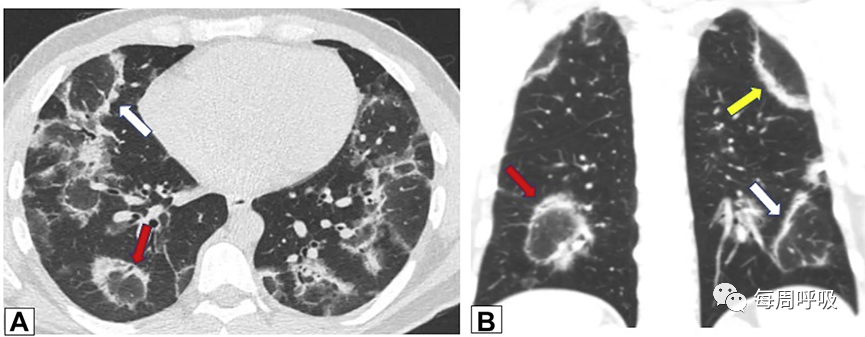

这种类型包括表现为线状不透明的实质条带,通常延伸到胸膜表面,通常先于磨玻璃样或实变(图15)。其他表现包括小叶周围增厚和具有反晕外观特征的病变(图16)。这个标志,也被称为“环礁征”,其特征是中央磨玻璃不透明(GGO)和外围实变。这些成像模式有着惊人相似的特征,通常可以在相同的情况下识别,甚至在同一张图像上。OP和慢性嗜酸性粒细胞性肺炎之间有相当多的共通之处,特别是当病变主要分布在上叶时。

图16 环礁征或反晕征。一名慢性持续性咳嗽和劳力性呼吸困难1年、体重减轻的32岁男性的CT扫描图像轴位(A)和冠状位(B)图像显示双侧中心磨玻璃样病灶完全被周围致密实变所包围,即反晕征或环礁征(A和B中红色箭头)。也存在不完全晕征(A和B中白色箭头)和小叶周围增厚(B中黄色箭头)。肺活检结果证实为机化性肺炎。